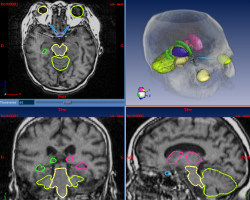

Cardiovascular system segmentation from MRI

In the context of the INRIA national action CARDIOSENSE 3D, this project is about the study of heart segmentation from MRI, using active models and statistical classification. The goal is to achieve the effective segmentation of the atria and proximal arteries in order to complete the current anatomical model where only ventricles are available. The simulation of the electromechanical activity of the heart on this model will participate in diagnosis and therapy of cardiovascular pathologies.

Contacts: Maxime Sermesant

Atlas-based Brain Critical Structures Segmentation for Radiotherapy Planning

Brain radiotherapy must achieve two goals: the complete irradiation of the tumor, and the preservation of critical structures (brainstem, eyes, optical tracts, etc.). By customizing the shape of the irradiation beam and modulating the irradiation intensity, conformal radiotherapy allows to optimize the irradiation of the tumor and the critical structures. The planning of conformal radiotherapy requires accurate localizations of the tumor and the critical structures.

This work aims to delineate automatically the critical structures of the brain. In order to do this in a specific patient’s image, we use an anatomical atlas containing labels of the structures of the brain. This atlas is registered on the patient image by a global followed by a non rigid registration. The aim of this work is basically to develop a non rigid registration algorithm adapted to anatomical structures registration. The second goal is then to validate the method we propose using quantitative measures on manually delineated patients.

Contacts: Grégoire Malandain.